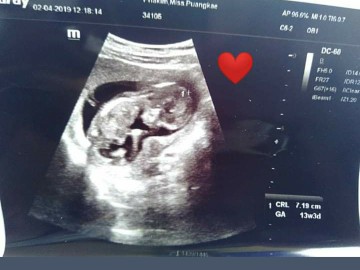

13w5dค่ะ